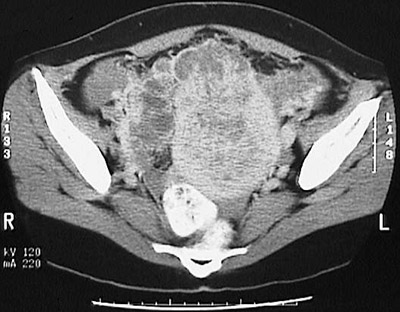

This abdominal CT scan view of the pelvis demonstrates a solid and cystic mass in the region of the uterus extending into the pelvis which is consistent with a choriocarcinoma.